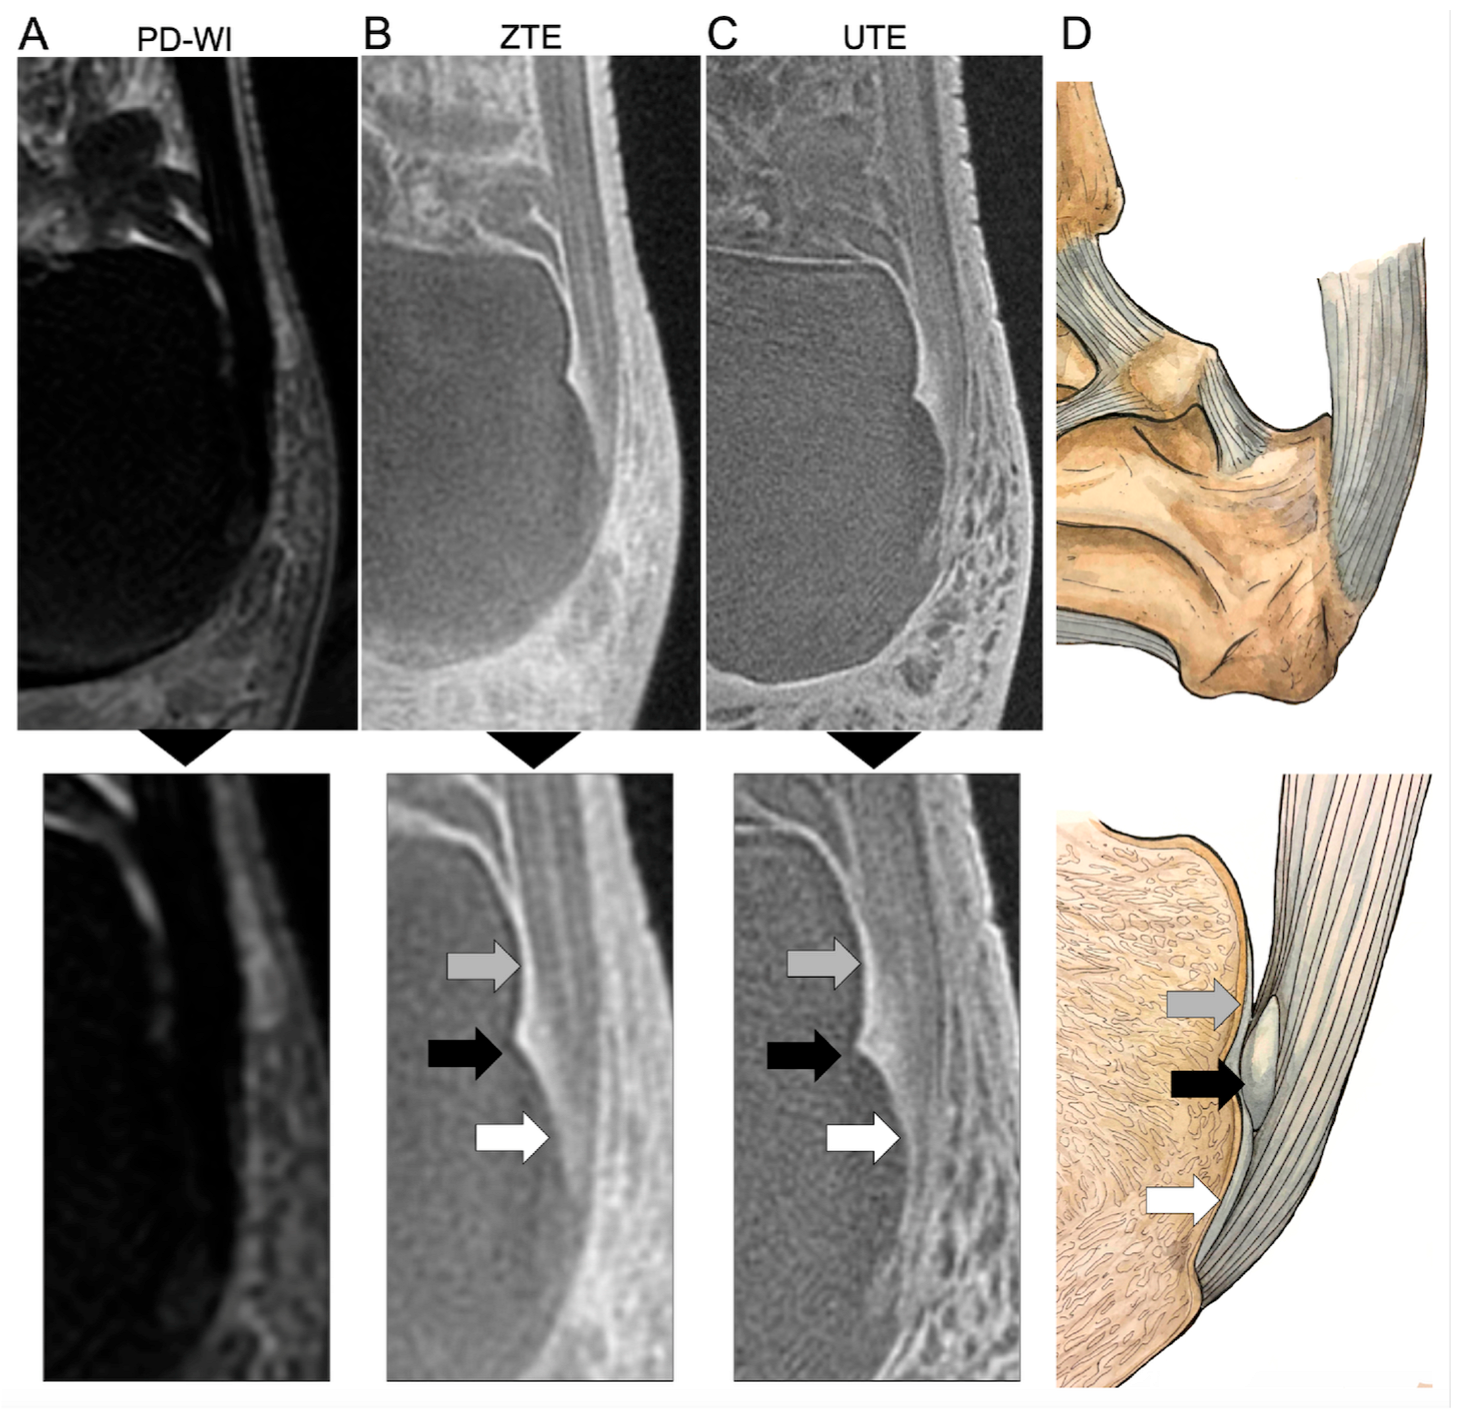

For each type of MR sequence (PD-WI, UTE, and ZTE), they assessed (i) whether each of the three components of the Achilles enthesis was clearly individualized or not, namely the ECa, SCa, and PCa. They concluded whether (ii) the entire anatomy was clearly distinguishable. Figure 1 represents this normal anatomy and its correspondence on UTE and ZTE. Next, for each of these fibrocartilages (ECa, SCa, and PCa) and for each sequence type, they indicated (iii) whether they considered the aspect normal, pathological, or doubtful.

Figure 1 shows an example of the entire anatomy of the Achilles tendon correctly identified on UTE and ZTE sequences but not on PD-WI. Table 2 summarizes the assessment of the Achilles enthesis anatomy with UTE, ZTE, and PD-WI.

The PCa was correctly seen on 0/50 (0%) patients using PD-WI, 48/50 (96%) patients using ZTE, and 38/38 (100%) using UTE (Figure 3A). This proportion was significantly higher with UTE versus PD-WI (p < 0.0001) and ZTE versus PD-WI (p < 0.0001) but not between UTE and ZTE (p = 1).

The SCa was correctly seen on 0/50 (0%) patients using PD-WI, 36/50 (72%) patients using ZTE, and 35/38 (92.1%) using UTE (Figure 3B). This proportion was significantly higher with UTE versus PD-WI (p < 0.0001), ZTE versus PD-WI (p < 0.0001), and UTE versus ZTE (p = 0.0269).

The ECa was correctly seen on 1/50 (2%) patients using PD-WI, 48/50 (96%) patients using ZTE, and 38/38 (100%) using UTE (Figure 3C). This proportion was significantly higher with UTE versus PD-WI (p < 0.0001) and ZTE versus PD-WI (p < 0.0001) but not between UTE and ZTE (p = 1)

Finally, the entire anatomy of the enthesis was correctly identified on 0/50 (0%) patients using PD-WI, 36/50 (72%) patients using ZTE, and 35/38 (92.1%) using UTE (Figure 3D). This proportion was significantly higher with UTE versus PD-WI (p < 0.0001), ZTE versus PD-WI (p < 0.0001), and UTE versus ZTE (p = 0.0269).

Figure 1. Assessment of the normal hindfoot and Achilles tendon ‘enthesis organ’ on proton density weighted imaging (PD-WI) ((A), upper panel) with magnification (lower panel), zero echo time imaging (ZTE) (B), and ultrashort echo time imaging (UTE) (C) MRI sequences and a corresponding representation of the real anatomy (D). The enthesis organ is made of three anterior fibrocartilages, all imperceptible with PD-WI, but demonstrating high signal intensity on UTE and ZTE sequences. The gray arrow shows the periost fibrocartilage (PCa) as a thin line at the posterior and superior surface of the superior tuberosity of the calcaneum. The black arrow shows the sesamoid fibrocartilage (SCa) as a ground-glass area within a notch at the middle of the posterior surface of the calcaneus. Lastly, the white arrow shows the enthesis fibrocartilage (ECa) at the interface of the tendon itself and the bone. The stripes on the Achilles tendon correspond to the endotenon (with high signal intensity on UTE and ZTE) and the tendon fascicle (with lower signal).